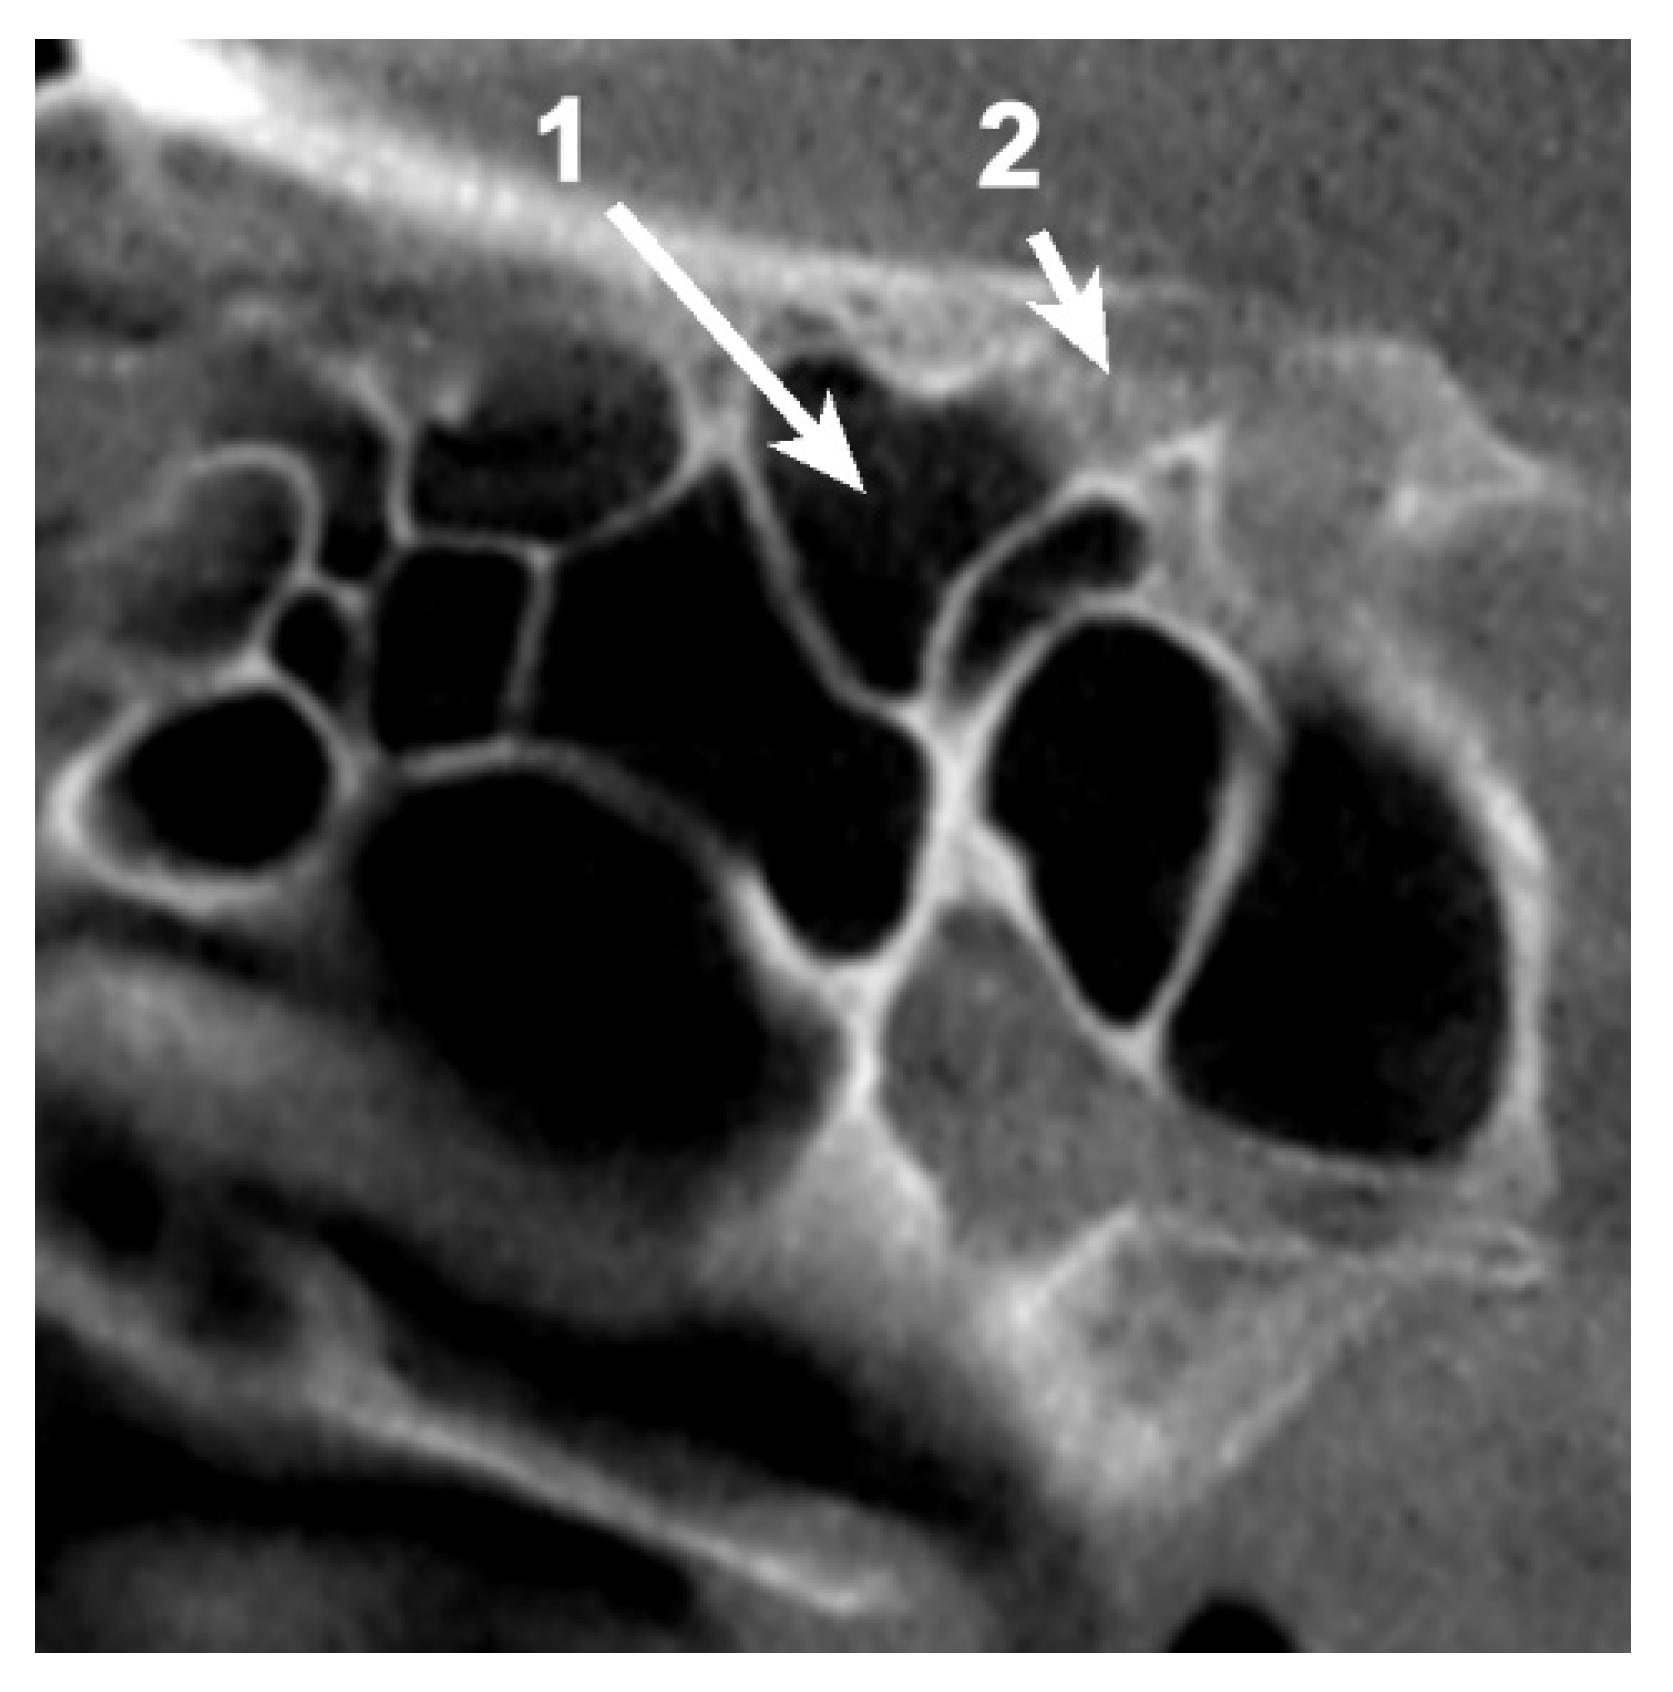

A total of 85 OS (53.12%) were pneumatized. The prevalence of OS pneumatization within the total was 67.5% (45 female and 9 male patients), 42.6% (23 cases) of them being unilateral (Table 1) (Figure 1 and Figure 2).

In 54/80 cases (67.5%), pneumatization within the OS could be identified (Figure 4). In eight cases (8.75%—six unilateral and two bilateral cases), the pneumatization of the sphenoid bone passed the OS, reaching the ACP.

Figure 1. Axial CBCT slice at the level of the left anterior clinoid process (ACP), demonstrating the unilateral pneumatization of the ACP via the optic strut (OS) from the sphenoid sinus. 1. Sphenoid sinus; 2. Pneumatized ACP; 3. Pneumatized OS.